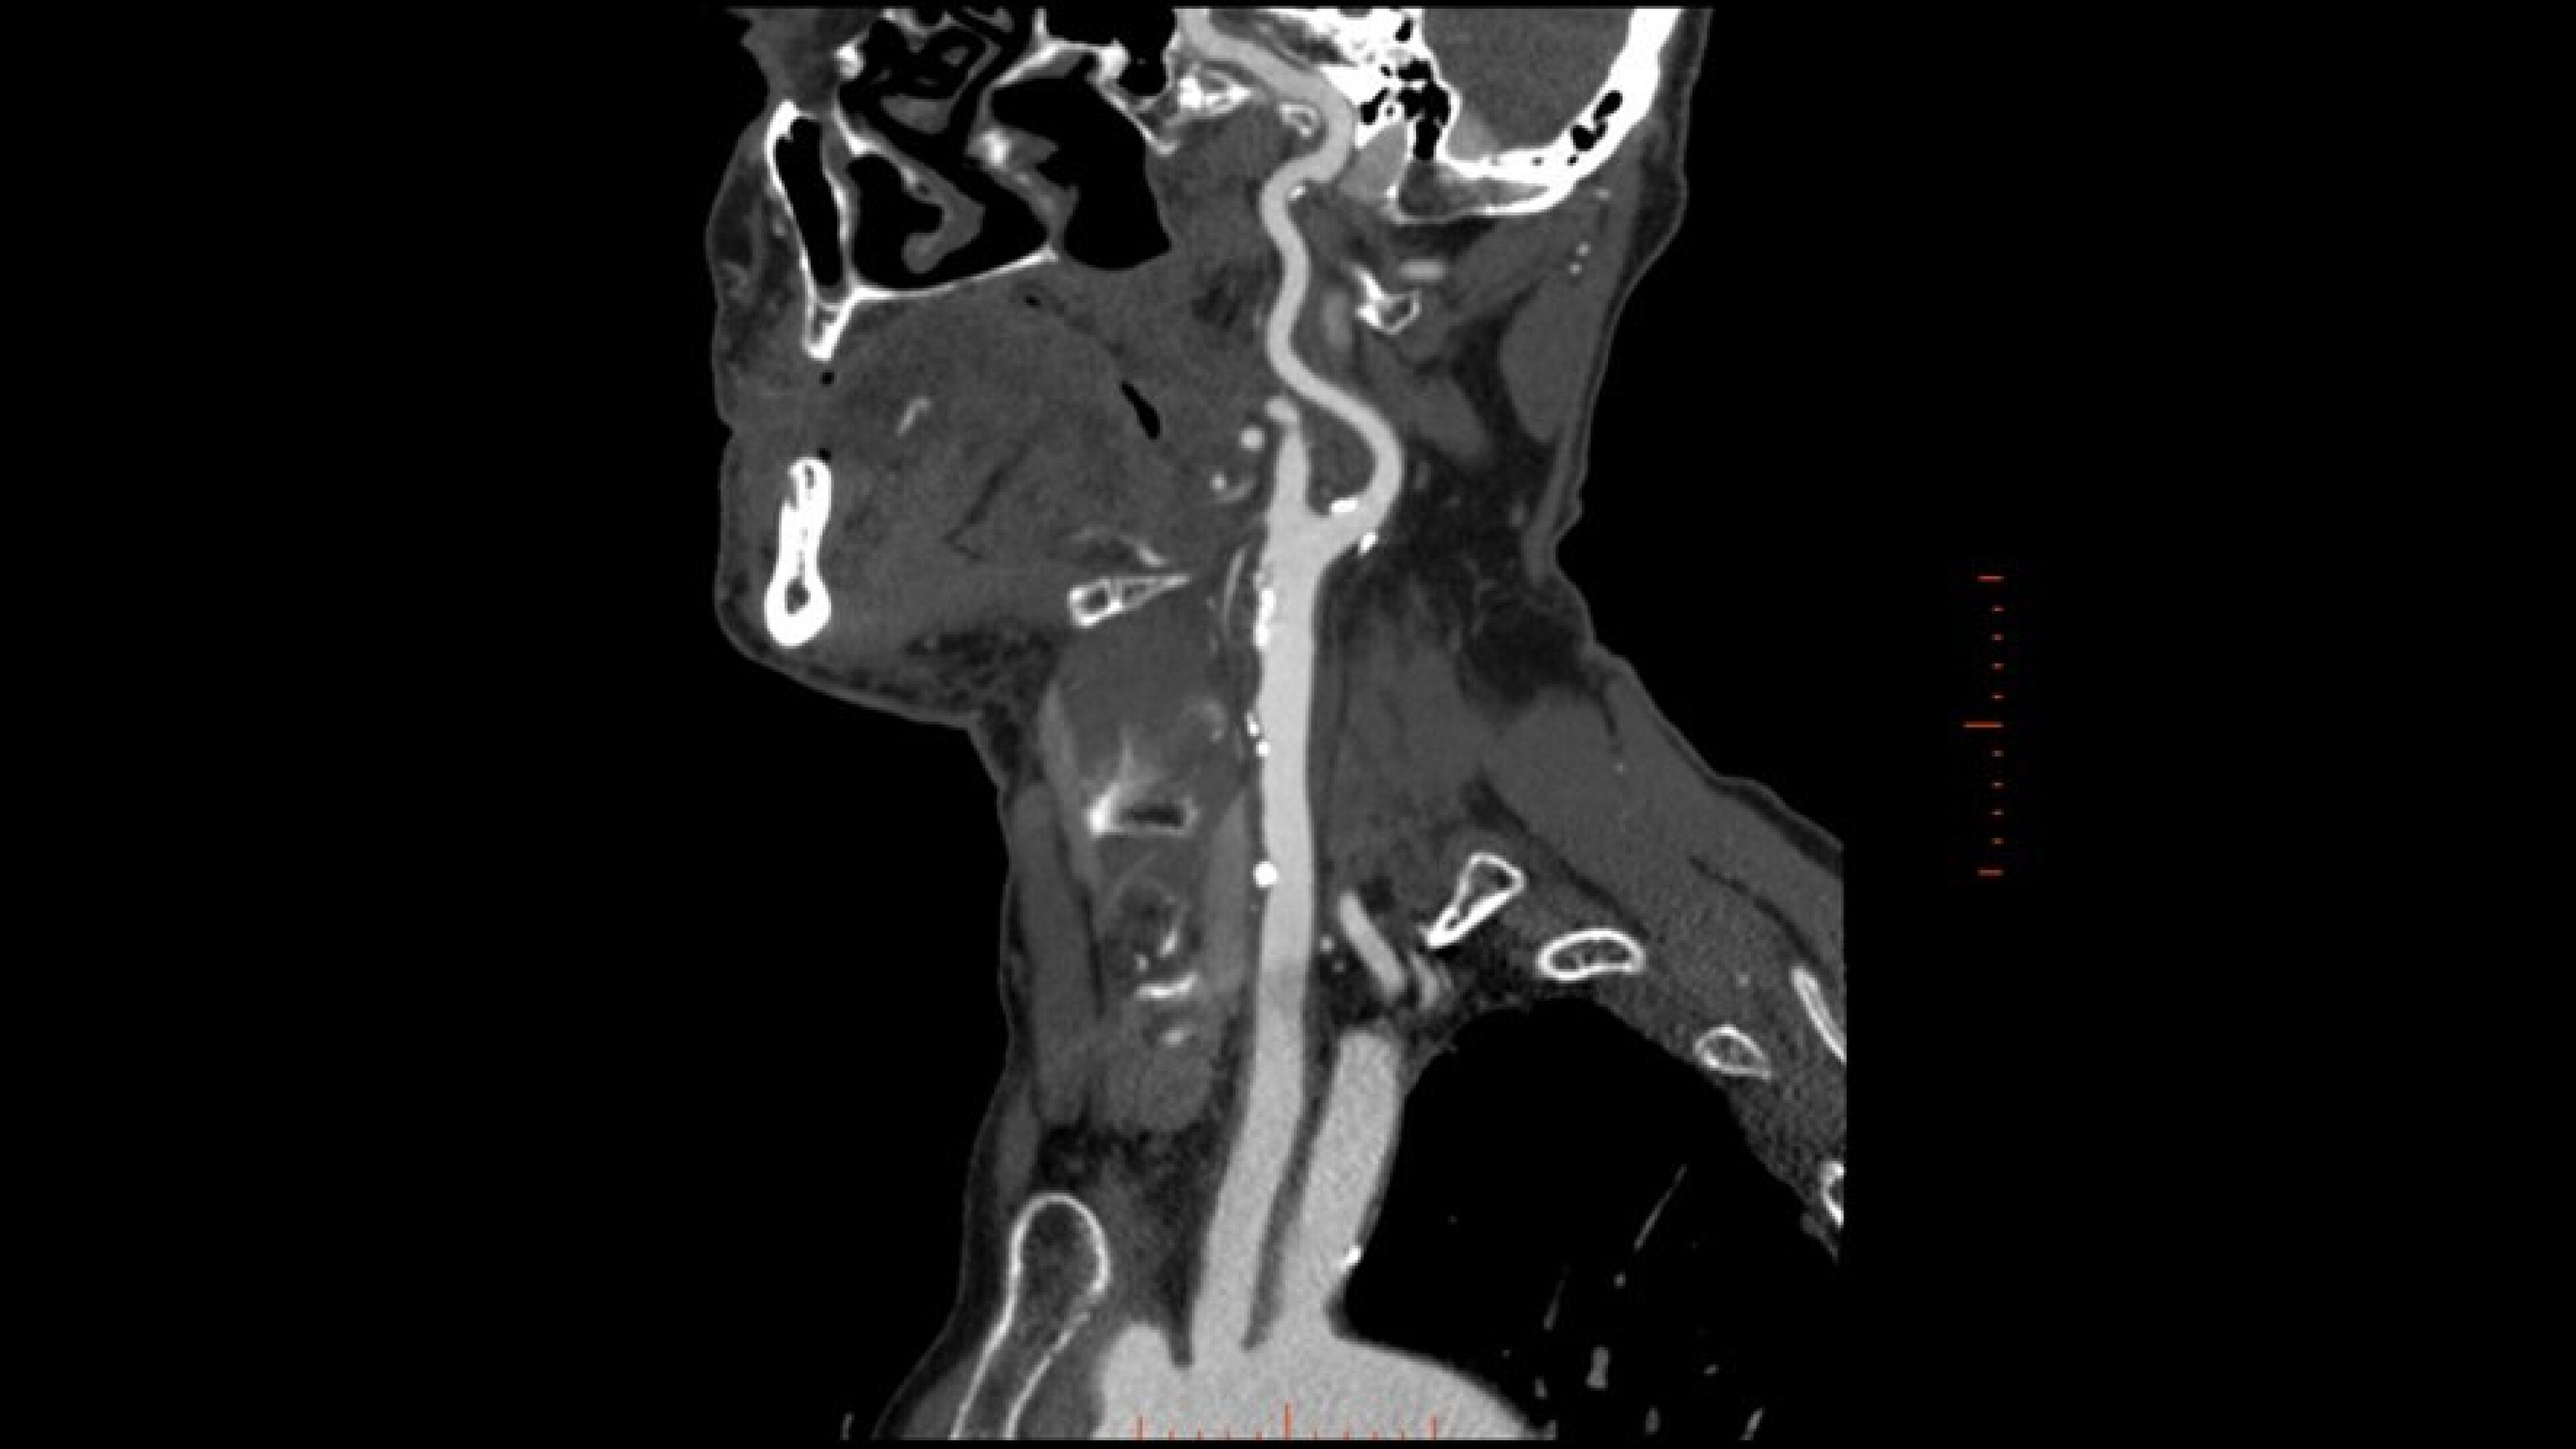

Autobone & VesselIQ Xpress

Fast and efficient vessel analysis from CT Angiography exams.

Zero-click bone segmentation and automated real-time fast tracking for all vasculature

Comprehensive stenosis measurement and plaque analysis of any vasculature

• Zero-click bone segmentation for head, neck, and other anatomy.

• Automated real-time fast tracking for all vasculature.

• Perform vessel analysis from any 3D or reformatted image with one or two clicks.